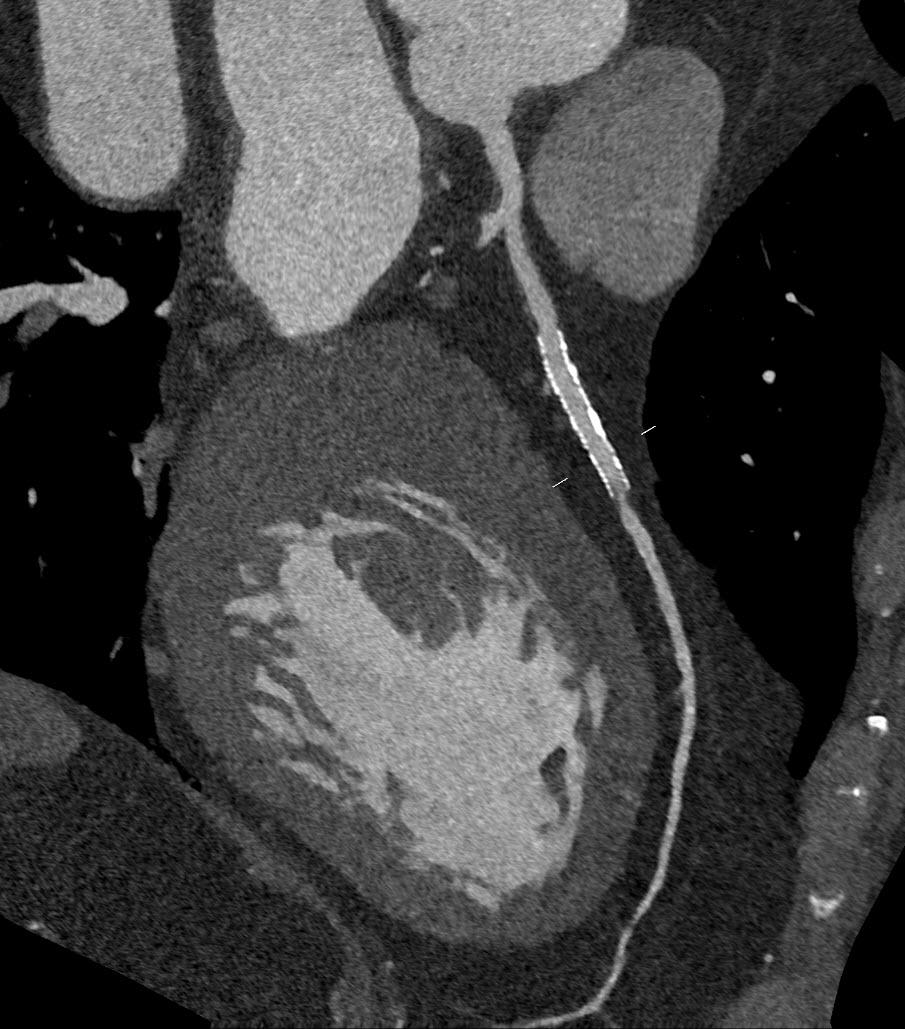

Kardio-CT: Tipps für eine erfolgreiche Herzbildgebung und häufige Fehler, die Sie vermeiden sollten – unabhängig an welchem System

Von Katrin Hägele – Ihre Expertin für moderne Bildgebungssysteme